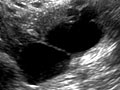

Ecografía pélvica

Una ecografía pélvica usa ondas sonoras para crear una imagen de los órganos y de las estructuras de la parte inferior del abdomen (pelvis).

Los órganos y las estructuras que son sólidos y uniformes (como el útero, los ovarios o la próstata) o que están llenos de líquido (como la vejiga) aparecen con claridad en una ecografía pélvica. Los huesos pueden obstruir la visión de otros órganos. Los órganos llenos de aire, como los intestinos, podrían hacer que la imagen no sea tan clara.

Una ecografía pélvica usa ondas sonoras para crear una imagen de los órganos y de las estructuras en la parte inferior del abdomen (pelvis).